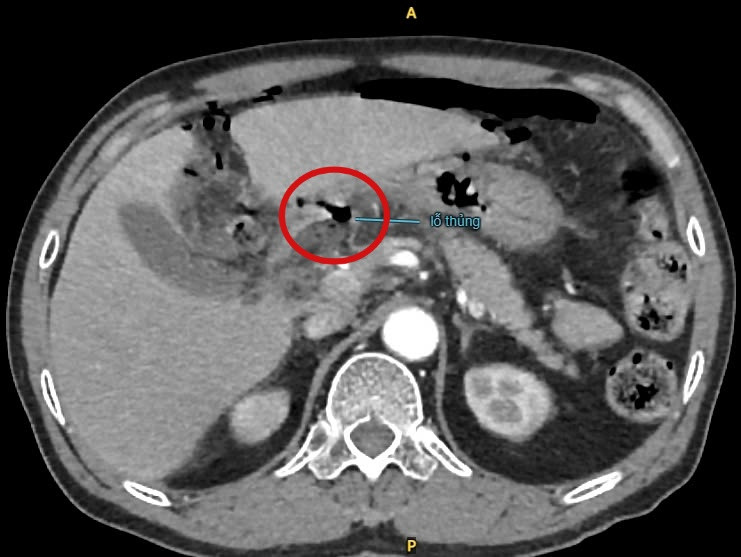

| Hình ảnh thủng tạng rỗng trên CT 160 lát ổ bụng - Ảnh BVCC |

BS.CKII. Nguyễn Vũ An – Trưởng khoa Ngoại Tổng Quát BVĐK Xuyên Á Long An nghi ngờ đây là trường hợp thủng tạng rỗng. Để xác định chẩn đoán, bác sĩ chỉ định chụp CT-scan ổ bụng ghi nhận: viêm phúc mạc do thủng tạng rỗng mặt trước tá tràng – hang vị. Phình động mạch chủ bụng đoạn dưới rốn thận – trên góc chia đôi động mạch chậu. Sỏi thận hai bên.